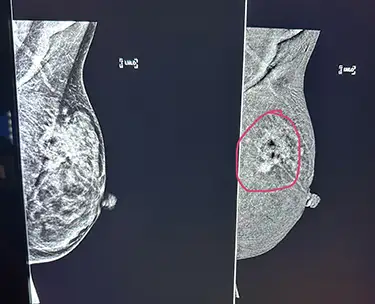

Myra Collins, lead mammographer with Novant Health East Cooper Medical Center, emphasized that mammograms are the first line of defense. “Many women are nervous about the compression paddle used during the mammogram,” she said. “At East Cooper, we use a radiolucent cushion to ease discomfort, and we offer 3D and contrast-enhanced mammography, especially for women with dense breasts. The technology has come a long way.”

On the imaging side, Collins said contrast-enhanced mammography is a game changer. “It’s especially helpful for patients with dense breast tissue or for those who can’t tolerate MRI. It highlights areas of increased blood flow, which can indicate cancer. We’re catching more cancers earlier, which is the goal.”

If you’re heading to your mammogram appointment, Collins has some practical advice: “Limit your caffeine and chocolate intake beforehand because they can make your breasts more sensitive. Also, don’t wear deodorant that day; the residue can mimic calcifications on your scan, which sometimes complicates interpretation.”